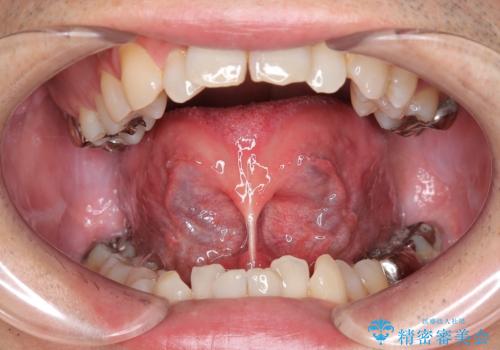

奥歯に虫歯があると言われた セラミッククラウンでキレイで長持ちする歯へ

担当医 榊原康平